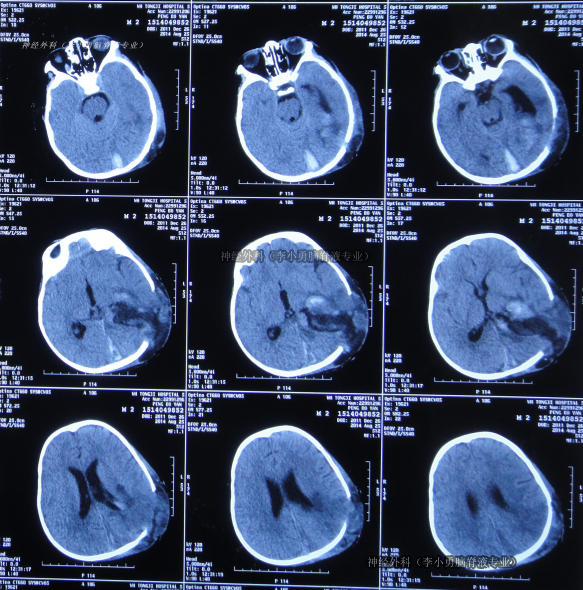

左额叶-胼胝体肿瘤卒中 侵犯对侧额叶 急诊开颅切除 镜下全切

脑血管-烟雾病

脑血管-动脉瘤

脑血管-动静脉畸形

脑血管-硬脑膜动静脉瘘

脑血管-海绵状血管瘤/畸形

神经介入-其他

脑肿瘤-胶质瘤

脑肿瘤-脑转移瘤

脑肿瘤-脑膜瘤

卢云鹤 关注

上海蓝十字脑科医院/同济大学附属脑科医院前天10:07 76阅读 0评论 1点赞 -